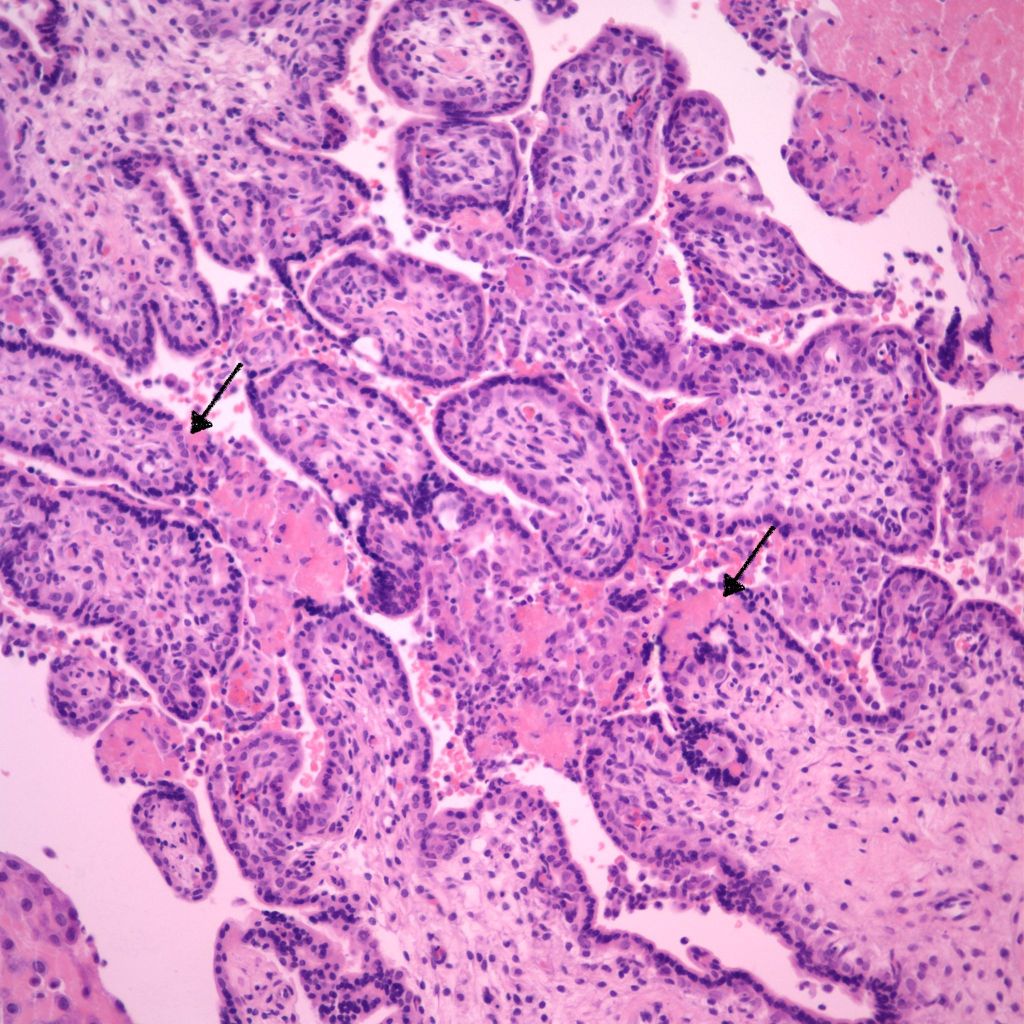

CHIV with prominent perivillous fibrinoid deposition

CHIV associated with Villitis of Uknown Etiology (VUE)

This pattern could be due to a primary cause of VUE with incidental chemotaxis of monocytes, two pathogenetically interrelated processes, or an incidental focus of VUE in a predominant CIIV disease. Currently, describing the extent of each process and its colocalization or lack of may prove useful until a better way to classify the co-existing lesions can be developed. One study has shown that there is a dichotomy between cases with c4d staining and those without c4d staining18.